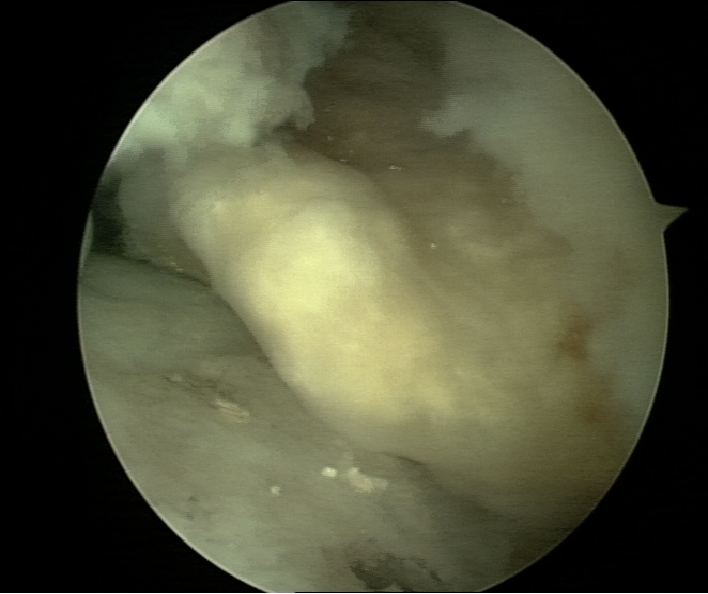

剥脱性骨软骨炎

王会余 男  65岁

软骨剥脱